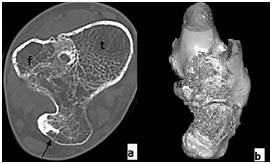

Because of unusual localization and for showing the relation of tumor with adjacent bony and soft tissue structures, CT and MRI exams were done. At axial and 3D CT images, there was a well-bordered tumor, originated from posterior aspect of distal metaphysis of tibia and fibula, with an own cortical and medullary bone in a continuity with the natives, and presented as tibiofibular synostosis via an osteochondroma (Figure 2). Calcified cartilage cap was seen as amorphous density at CT image and, isointense with bony cortex on T1 weighted (T1W) and T2 weighted (T2W) images.

Figure 2A & B Axial (A) and 3D CT (B) images showing an osteochondroma (arrow) origined from both tibia and fibula, resulting in a synostosis. T, tibia, f, fibula.